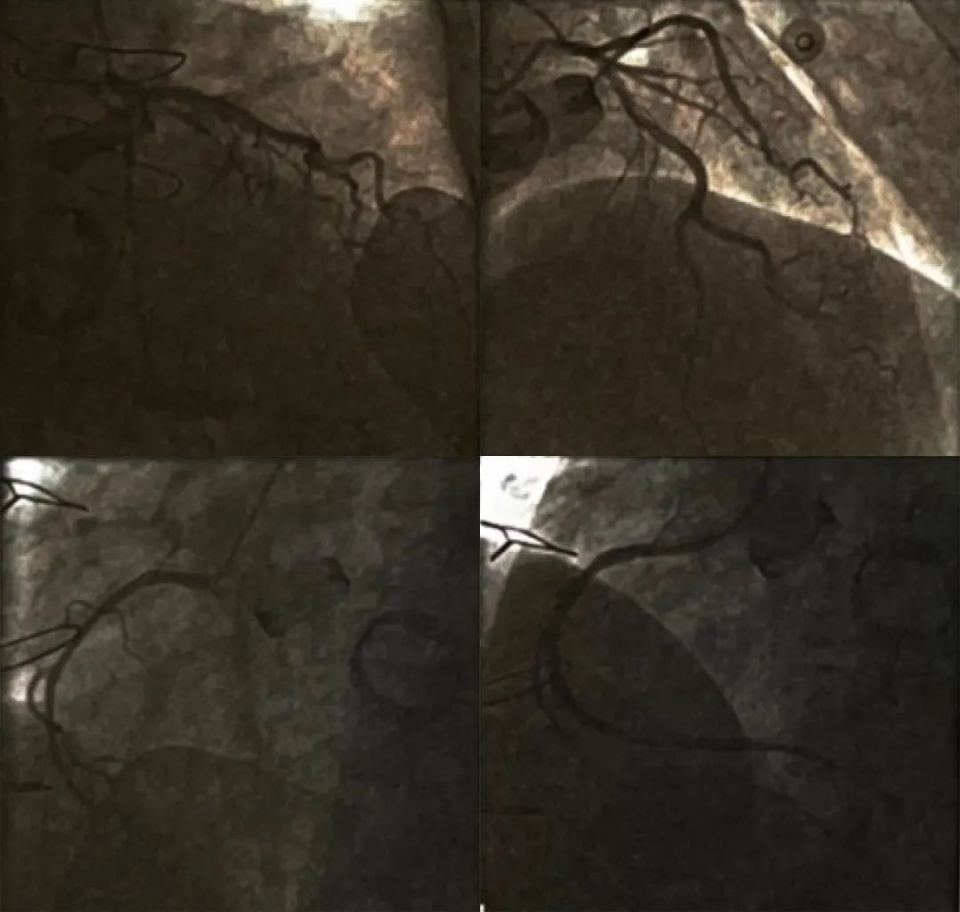

患者诊断考虑再发急性心肌梗死,行急诊冠状动脉造影(图2),示左冠状动脉正常,右冠状动脉支架的中远段血栓形成,完全闭塞,行血栓抽吸,抽出少量血栓。后用2.0mmx15mm的球囊进行扩张,扩张后右冠状动脉远端显影,血栓负荷仍然很重。再次行血栓抽吸,后血栓负荷仍较重,换用3.5mmx12mm的球囊进行扩张,远端血流改善,但支架内仍可见明显血栓影。PD血流TIMI I级。反复进行球囊扩张后,PL和PD血流改善,结束手术。考虑亚急性支架内血栓形成,血栓负荷重,给予阿司匹林、氯吡格雷、欣维宁三联强化抗血小板+华法林抗凝治疗,逐渐调整华法林剂量,INR值大部分时候维持在2~3,肌钙蛋白I呈进行性下降。

图2. 第二次冠状动脉造影及PCI

回旋支正常;前降支正常;右冠中远段(原支架近端)血栓性闭塞;血栓负荷仍重,但远段血流恢复TIMI Ⅲ级